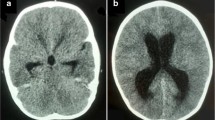

A 1-year-old patient, product of preterm gestation because of premature rupture of membranes, and previously healthy, presents with vomiting and irritability. Communicating hydrocephalus is evident in computed tomography (CT); VPS is placed, and 45 days after surgery, the patient developed ascites. CT abdomen shows free fluid in the cavity, without a solid or hollow viscera lesion. VPS is externalized, reporting drainage volumes of 1000–1200 ml/day of CSF, without signs of infection. Given such high output, magnetic resonance imaging (MRI) is performed showing bilateral CP hyperplasia (Figs. 1 and 2). The bilateral endoscopic procedure is performed in 2 stages: first, only CP cauterization (CPC). Subsequently, CSF flow decreases by 800 ml/day, and bilateral plexectomy was performed using a right frontal approach and performing a posterior septostomy, decreasing CSF outflow to 120 ml/day. It is decided to install VPS. A biopsy confirmed the diagnosis of CP hyperplasia.